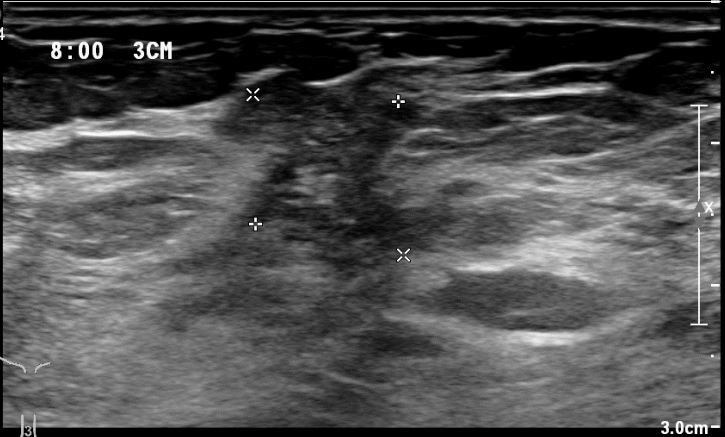

상기환자 외부검사상 이상소견으로 내원하신 40대 후반의 여성분으로

우측유방의 의심스러운 혹 조직검사시행후 유방암 진단되었읍니다